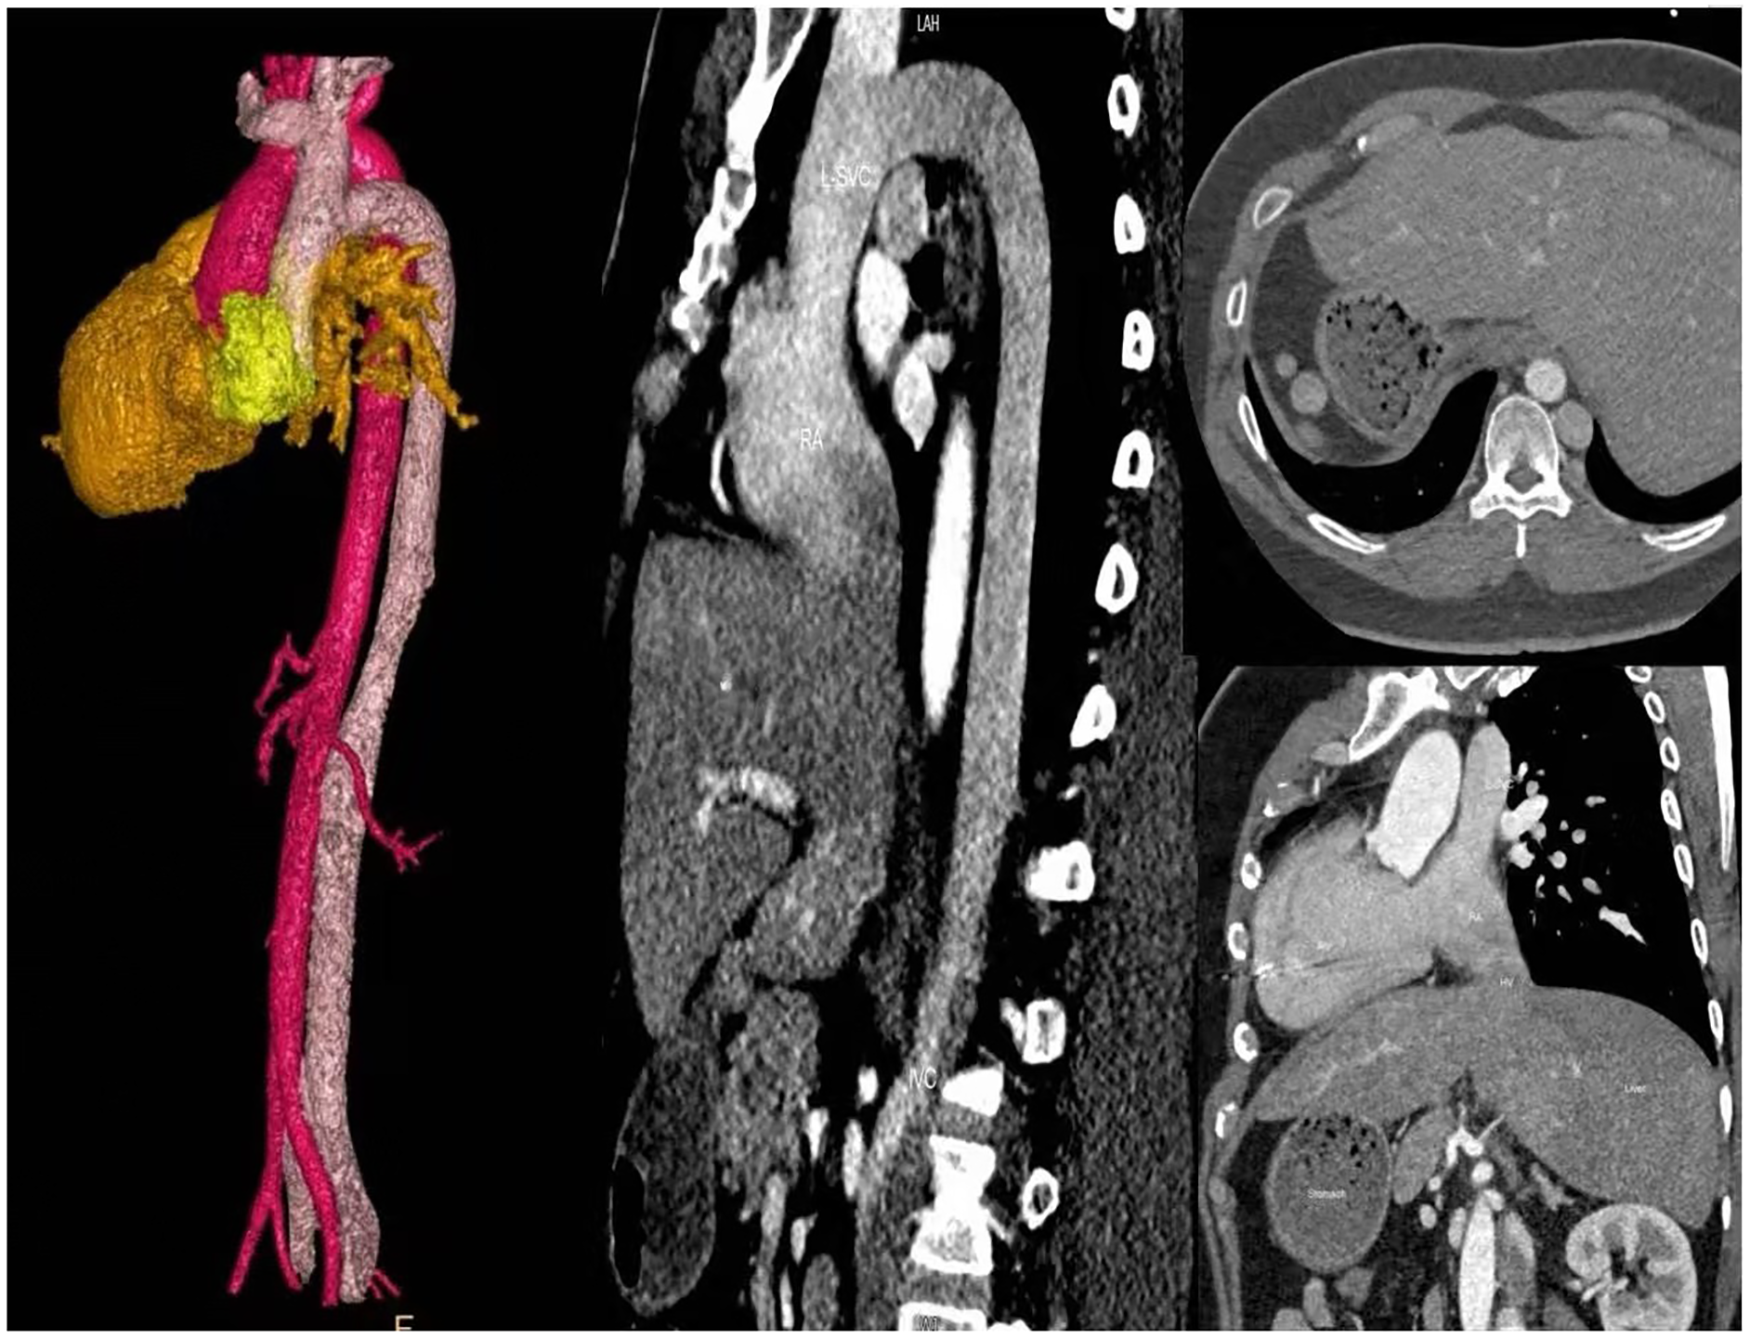

Echocardiography revealed mirror-image dextrocardia, a post-VSD repair status, and no evidence of ventricular-level shunting. Electrocardiography (performed with left and right hand electrodes reversed) demonstrated sinus rhythm, third-degree AVB, junctional escape rhythm, and complete right bundle branch block (Figure 1A). Chest radiography confirmed mirror-image dextrocardia (Figure 1B). CTA of the great vessels showed that the IVC was located on the left side of the aorta, with absence of its hepatic segment. The IVC ascended and connected to the right superior vena cava via a dilated azygos vein. The suprarenal portion of the IVC exhibited luminal stenosis, with the narrowest diameter measuring approximately 8.5 mm, while the hepatic veins drained directly into the right atrium (Figure 2). The patient fulfilled the Class I indication for pacemaker implantation (6). However, he declined a conventional lead-based pacing system and instead opted for leadless pacemaker implantation.

Figure 2

Chest and abdominal large vessel CTA: Absence of the hepatic segment of the inferior vena cava (IVC); the left-sided azygos vein is thickened and extends to the right superior vena cava (SVC); hepatic veins drain directly into the right atrium.